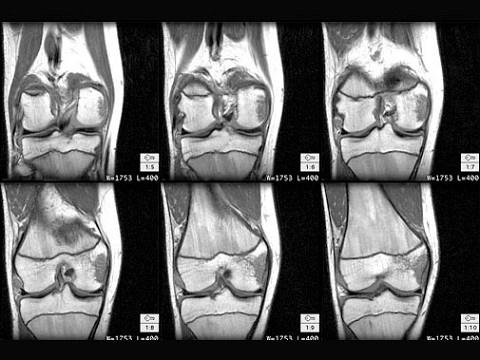

问题 男,45岁,有外伤史,请结合所提供的图像,选择最佳选项 ( )

选项 A、半月板损伤 B、后十字韧带撕裂 C、前十字韧带撕裂 D、股骨髁内侧挫伤 E、未见异常

答案 D